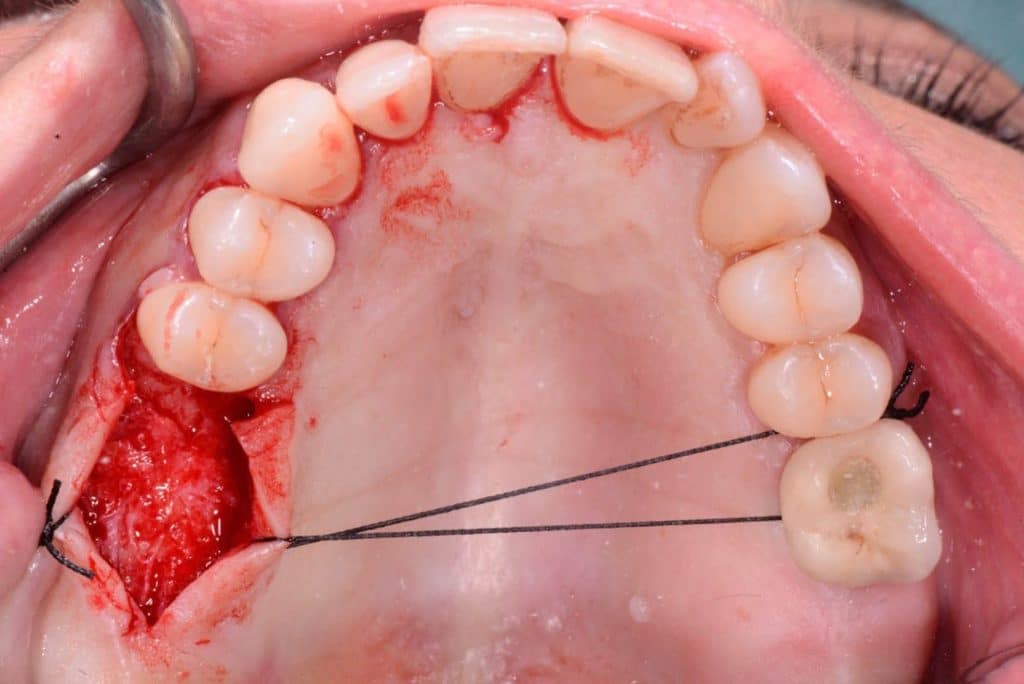

The crest is cut with a size 15 Bard-Parker scalpel, and a full-thickness flap is made performing a double widening suture both buccally and palatally. The first bur to be used is the Locator Drill that works only for 3.5 mm and only drills the cortical bone.Subsequently, I used the 1.2 mm diameter Probe Drill.

Two 8mm Straumann Wide-Neck have been inserted. After inserting a healing abutment with a height of 2 mm, a detached stitches suture was made. Good planning allowed me to be precise with the incision, and only 2 stitches have been necessary.